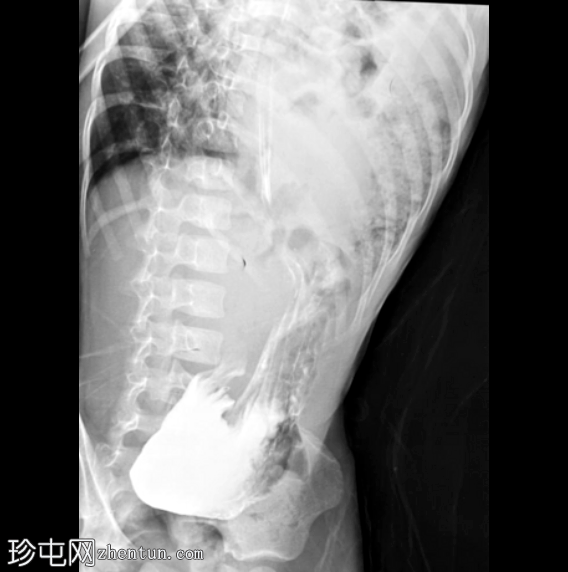

冠状面

非造影

左侧膈疝通过位于左膈中部的一个缺损形成,伴有纵隔向右侧移位,下方左塌陷。

脾脏、大肠和小肠均有疝气,同时伴有肠系膜上血管疝气。

胃位于下部,靠近主动脉分叉处。

在降结肠和直肠中可见先前荧光透视检查的残留造影剂。